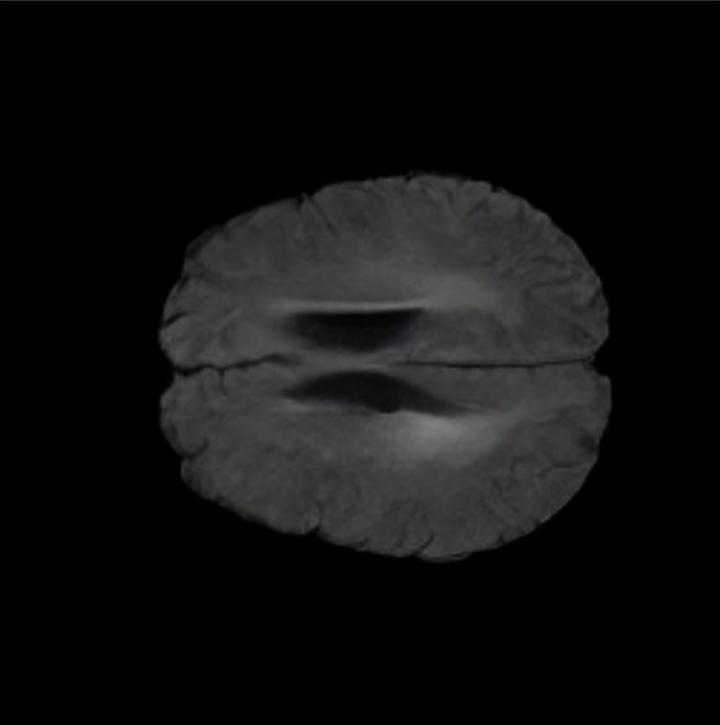

Notably, X-Diffusion achieves sota dB for a few input slices while baselines require more than 60 input slices to achieve similar performance (Figure 7). The margin is more than 12 dB PSNR for the 1-slice input in both the BRATS and the UK Biobank benchmarks (see Table 1 and Figure 6). For reference, two randomly sampled MRIs from the UK Biobank would have a PSNR of 15.95 dB 0.36 (on 4800 randomly sampled examples). The slices from 3D reconstructed volumes at varying depths and axis of rotation visually match the ground truths (see Figures 5 and Figure 4). We also plot the error map (Figure 4) of such X-Diffusion generations to highlight the differences with the ground truth MRIs.

Tumour Information Preservation. For the brain tumor segmentation, we use a Swin UNETR model[27, 70], trained with random rotation, and intensity as data augmentation. In Figure 5, we highlight the tumor profiles of the generated MRIs compared to the ground truth tumour profile. In the test set with human ground-truth annotations (), the real MRI Dice score is 85.15 while the generated MRIs from a single slice have a dice score of 83.09. This shows how the generated MRIs indeed preserve the tumor information and can act as an affordable and informative pseudo-MRI, before conducting an actual costly MRI examination in hospitals.

The comparison of generated MRIs versus reference MRIs suggests a nearly perfect preservation of brain volume (in mm3) with median volume of reference MRIs of versus generated MRIs (see an example of brain generation in Figure 11).